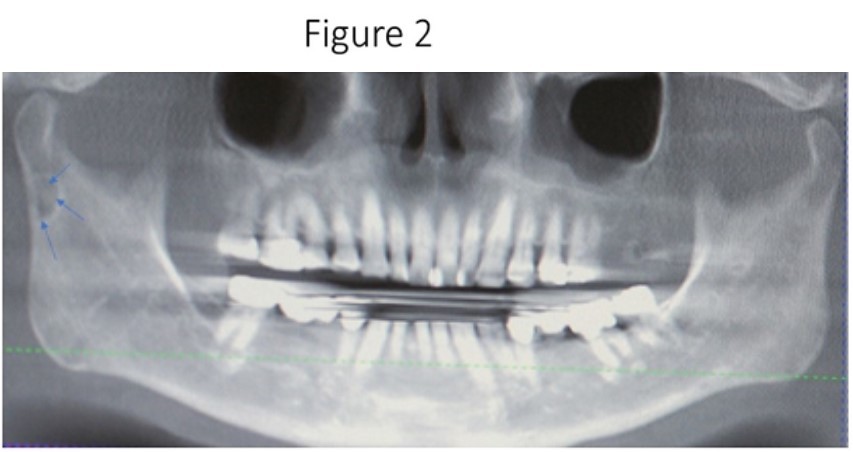

Maxillofacial examination was unremarkable. No facial swelling, masses or asymmetry was observed. The TMJ examination was normal. No pain or tenderness to digital palpation was observed in the right preauricular region. Oral examination of the patient was unremarkable. No trismus was observed as the maximal interincisive opening was greater than 40.0mm. No anterior or posterior open bite was observed. Imagining studies to rule-out intraosseous neoplastic lesions and arrive at a definitive diagnosis consisted of a panoramic radiograph and cone beam CT scan (120 kVp, 5 mA, 7.4 sec). Panoramic radiograph revealed a unilocular, well-circumscribed radiolucency in the right subcondyalar region of the mandible that was close to the posterior border of the condylar neck (Figure 2). Cone beam CT scan (i-CAT FLX, Imaging Sciences, Hatfield, PA) imaging revealed a well-defined unilocular, elliptical shaped radiolucent lesion on the medial surface of the right subcondylar neck of the mandible (Figure 3, Figure 4, Figure 5). The elliptical shaped unilocular lesion involved almost the entire horizontal dimension of the subcondylar neck (Figure 4). Figure 5 shows the three-dimensional CT scan reconstruction (i-CAT FLX, Imaging Sciences, Hatfield, PA) of the medial defect in the subcondylar region of the mandible. Based on knowledge of clinical head and neck anatomy and imaging studies, no treatment was indicated as the diagnosis was consistent with a variant of a Stafne bone cavity of the right subcondylar neck near the parotid gland and not a pathological condition. The patient was informed about the risk of condylar neck fracture due to the critical size of the SBC.

Figure 2.Panoramic radiograph reveals a unilocular radiolucency in the right subcondylar neck of the mandible which is considered a variant of the classic SBC described by Dr. Stafne.